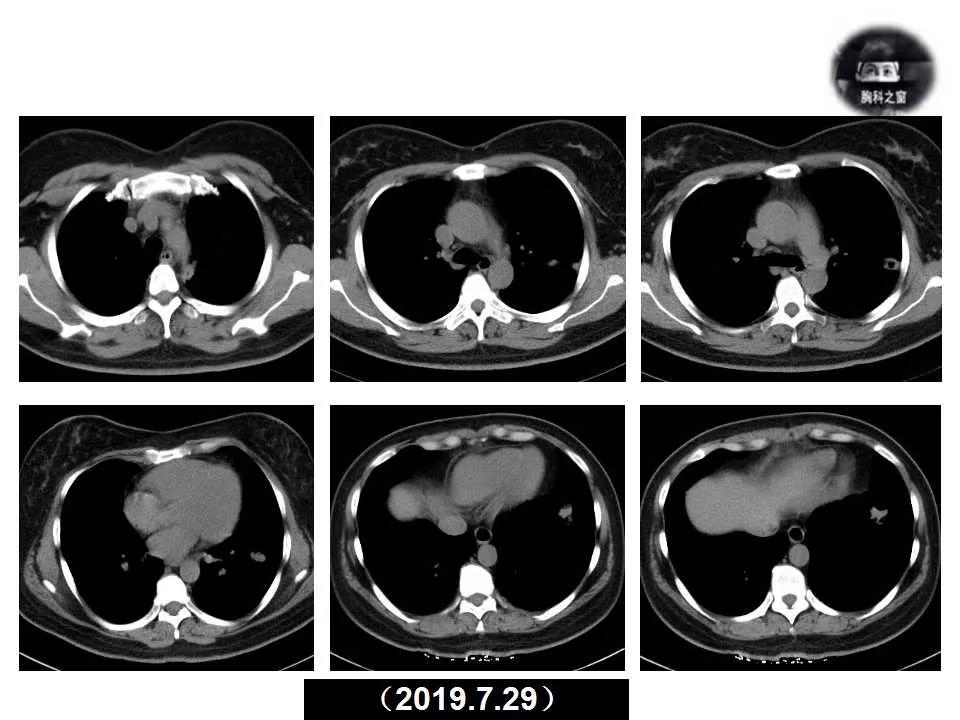

主诉:发现左肺病变1天

现病史:患者1天前体检胸部CT提示左肺病变,之前一段时间进食较少,七月初、七月中旬出现咳嗽、胸痛、无法深呼吸,无咯血,无乏力、盗汗,无明显体重减轻,为接受进一步诊治收入院。(2019.7.30)

影像诊断:真菌性肺炎,隐球菌可能性大。

追问病史,有近距离接触鸽子史。隐球菌抗原(+)。

肺隐球菌病